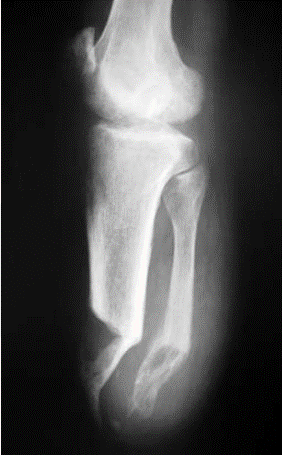

# Amputações - O que preconizar em amputações de **membros isquêmicos**?

- Não fazer miodese → **optar por mioplastia** - Deixar a **tíbia mais curta** (preferencialmente de **8,8 a 12,5 cm**) - Proporcionar um **flap posterior mais longo**

26

# Amputações - O que preconizar em amputações de membros **não isquêmicos**?

- Fazer **miodese** - Deixar a **tíbia mais longa** (de **12,5 a 17,0 cm**) ## Footnote *"Regra de 3": para cada **30 cm de altura** do indivíduo → deixar **2,5 cm (arredondando para **3,0 cm**) de coto***

27

# Amputações - Qual deve ser a **conduta para a fíbula** em casos de amputações a nível transtibial com **tíbia restante < 8,8 cm**?

- **Ressecção**

28

# Amputações - Na amputação transtibial, qual técnica operatória diminui a instabilidade tibiofibular proximal e proporciona um coto mais estável?

- **Sinostose tibiofibular distal (técnica de Ertl)**